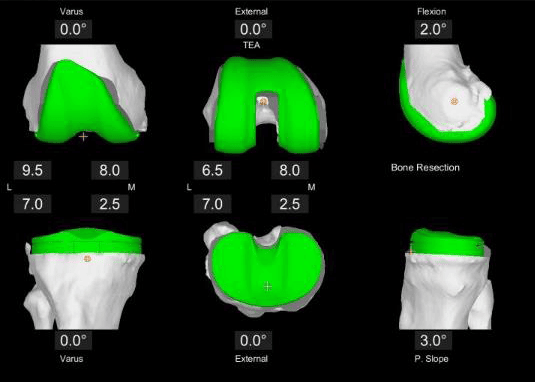

• Durch die CT-basierte 3D-Modellierung der Knochenanatomie können Chirurgen mit dem Mako System einen maßgeschneiderten Operationsplan erstellen und die gewünschte Implantatgröße, -ausrichtung und -passung anhand der individuellen Anatomie der betroffenen Person bestimmen. Das Mako System ermöglicht es Chirurgen auch, den Operationsplan intraoperativ auf virtuelle Weise zu ändern und unterstützt sie bei der Durchführung von Knochenresektionen.

Maßgeschneiderter Operationsplan: vor der Operation wird eine Computertomographie (CT) Ihres Kniegelenks durchgeführt. Auf dieser Grundlage wird dann ein virtuelles 3D-Modell Ihrer individuellen Anatomie entwickelt. Das 3D-Modell ermöglicht es Ihrem Chirurgen, Details zu sehen, die normalerweise nicht mit Röntgenbildern allein zu sehen sind. Die von Mako bereitgestellten Informationen helfen Ihrem Chirurgen bei der Bestimmung der gewünschten Größe und Positionierung Ihres Implantats. Während der gesamten Operation stellt Mako SmartRobotics™ dem Chirurgen Daten in Echtzeit zur Verfügung, damit er die Bewegung und Spannung Ihres neuen Gelenks kontinuierlich beurteilen und Ihren Operationsplan bei Bedarf anpassen kann.

Mit Mako SmartRobotics™ kann Ihr Chirurg einen maßgeschneiderten Operationsplan erstellen und mit Hilfe der AccuStop™ Technologie die für Sie geplanten Schnitte präzise durchführen, was für einige Patient:innen zum Erhalt von Weichteilgewebe und für andere zum Schutz von gesundem Knochen beitragen kann.

• Virtuelles 3D-Modell des Gelenks: ermöglicht die genaue Planung für jeden Patienten bzw. jede Patientin

• Individueller präoperativer Plan: für Plananpassungen und funktionale Implantatpositionierung.